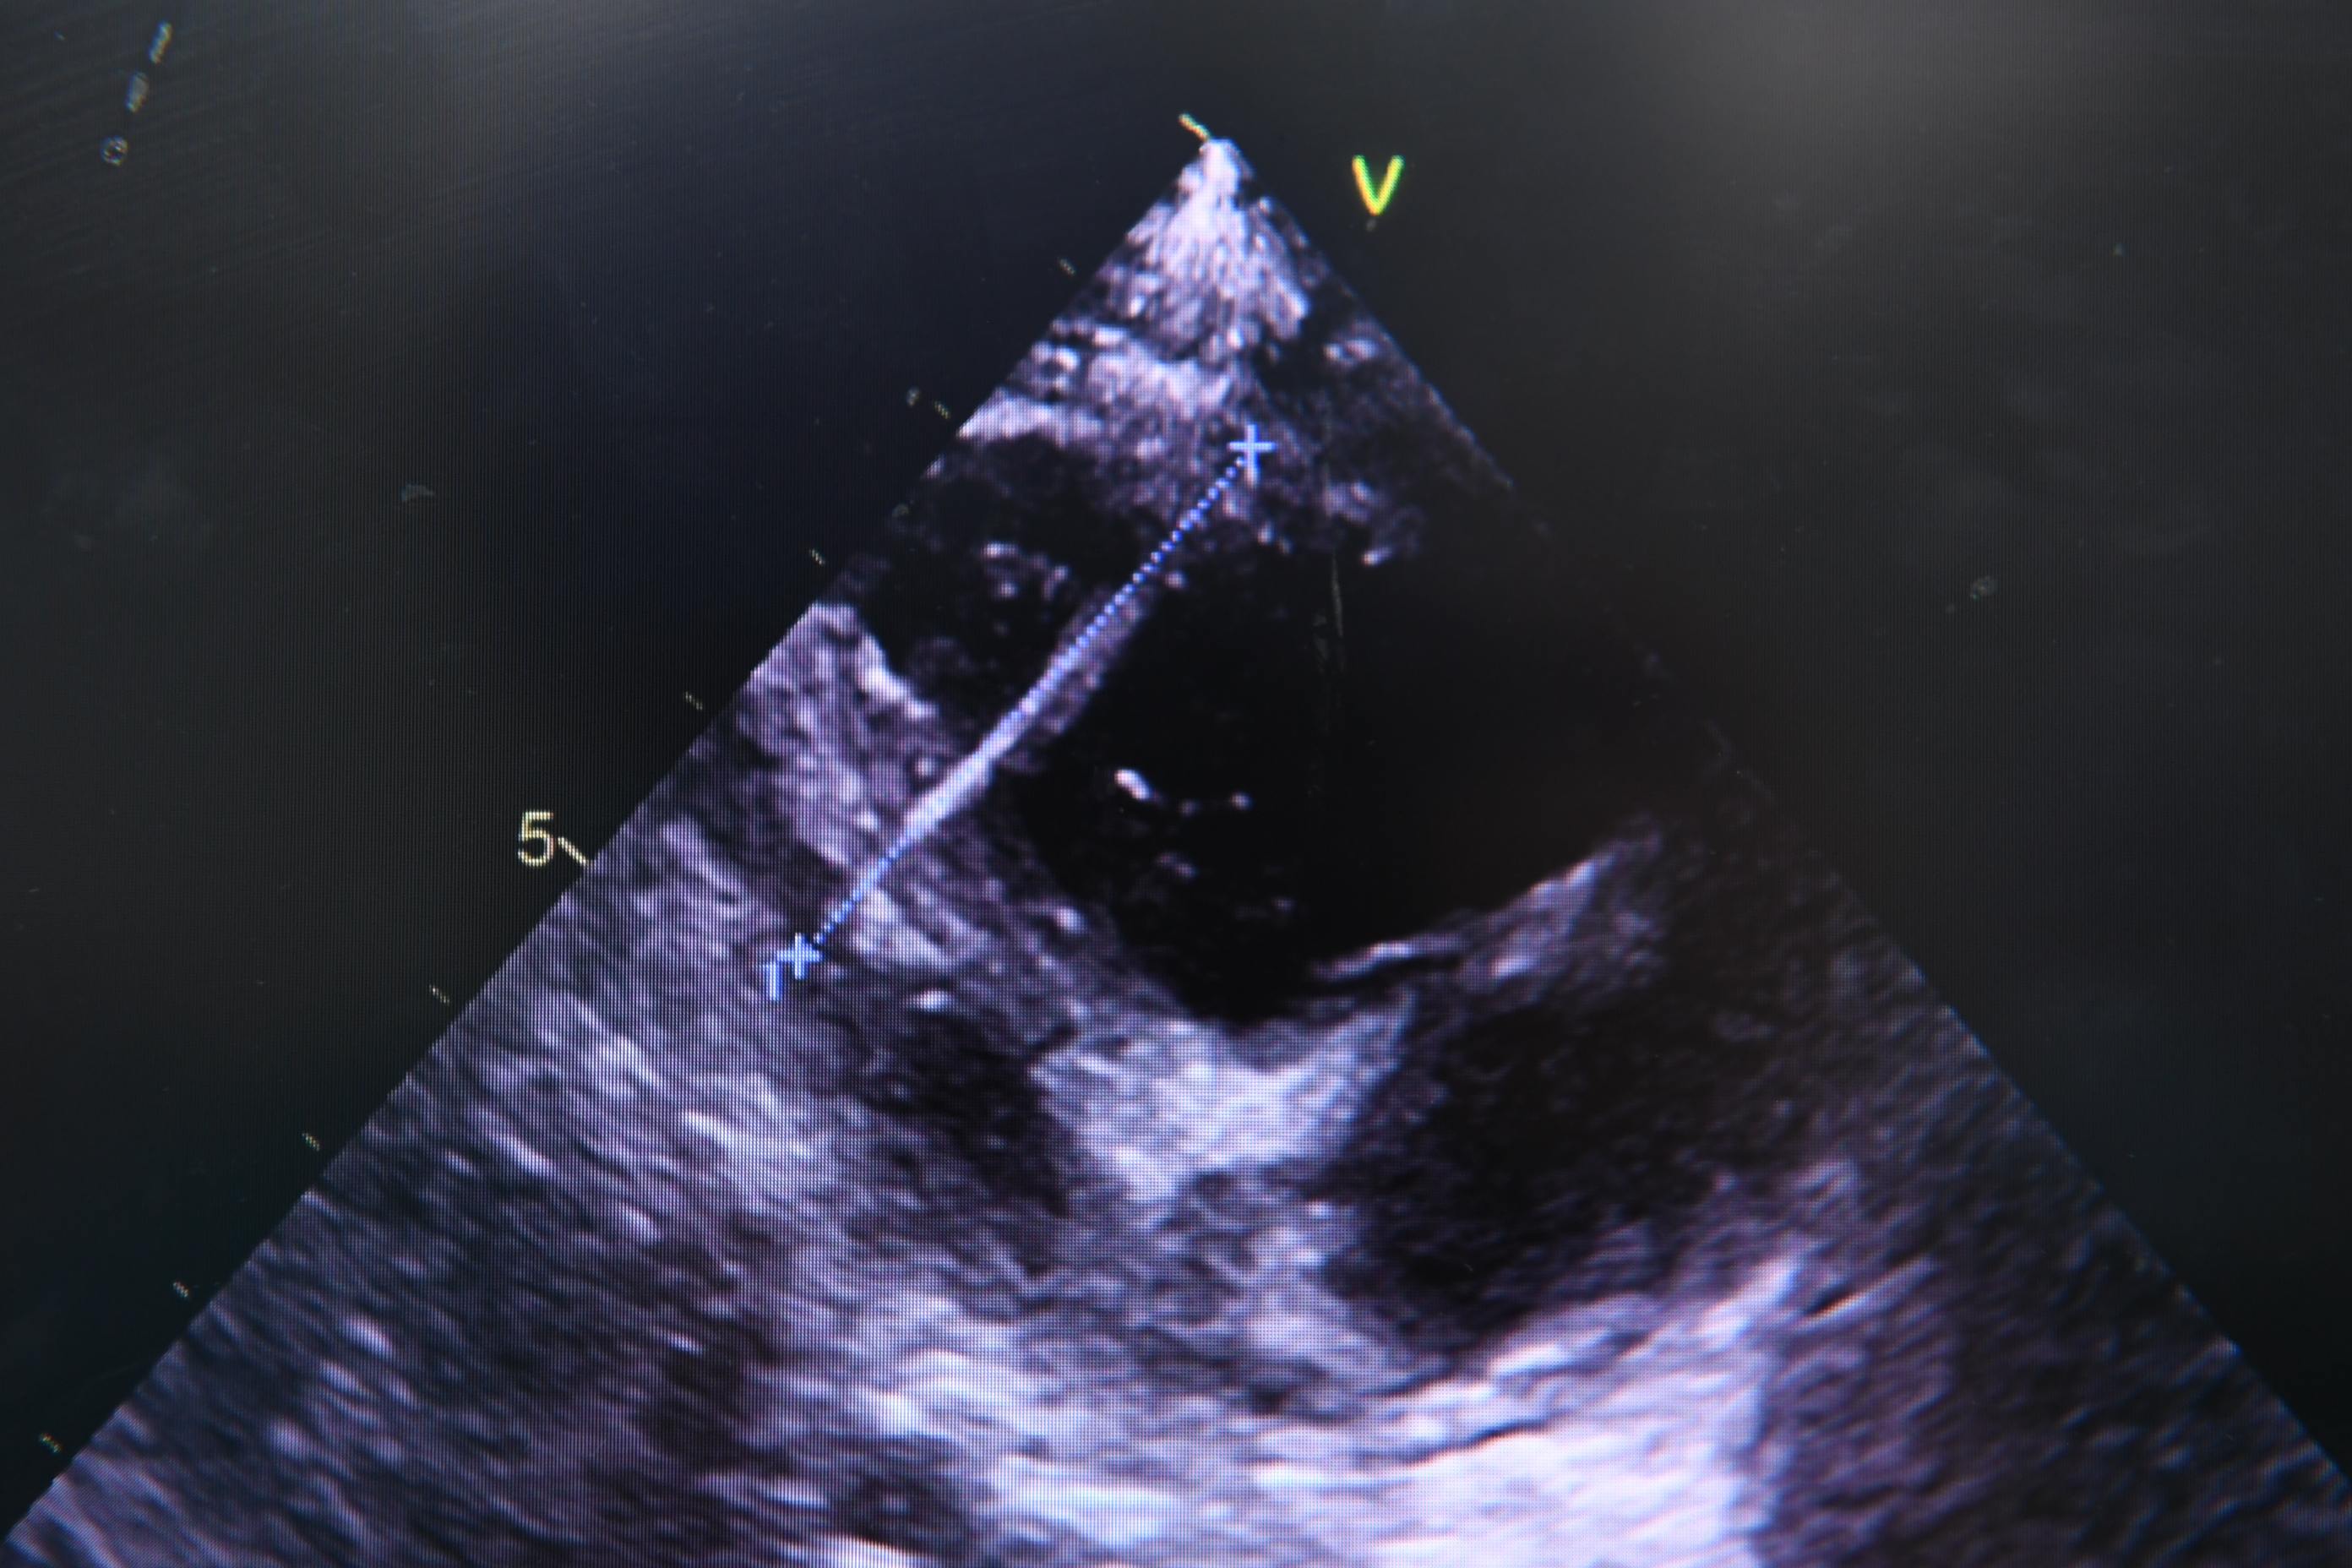

经过仔细检查,医生发现,土豆心脏内的钢针竟然长达4厘米,从右心室贯穿后扎入了左心室!

由于心脏有节律的收缩舒张跳动,钢针已经被带入心脏内部,在扎穿室间隔后,针体几乎完全扎入了心腔内,只在心脏表面留下个不足1mm的小尾巴。